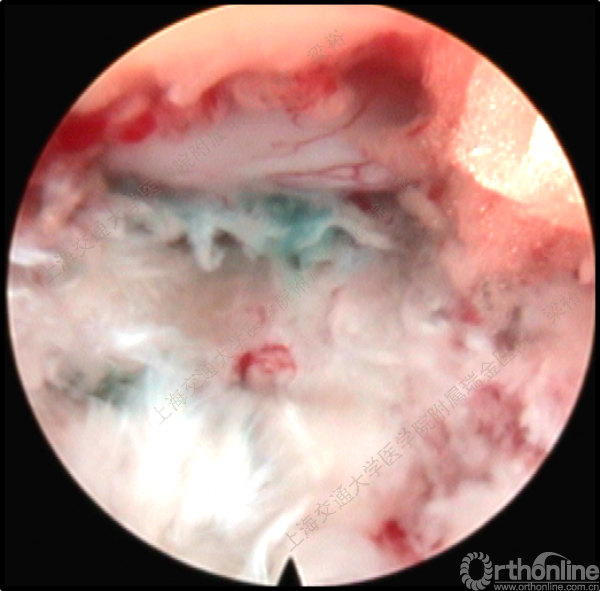

随着微创技术的发展以及手术经验的积累,脊柱微创手术已开始逐步取代传统的脊柱外科手术。微创手术已涉及从颈椎到腰椎的整个脊柱。从简单的椎间盘手术到复杂的 脊椎手术,手术类型越来越多样。在所有的脊柱微创手术中,尤其脊柱内镜手术在过去10年中取得了惊人的进步。在技术发展的同时,脊柱内镜的手术并发症问题也逐渐浮出了水面,针对脊柱内镜手术的并发症与其对策,上海交通大学医学院附属瑞金医院梁裕教授介绍了他们的经验。